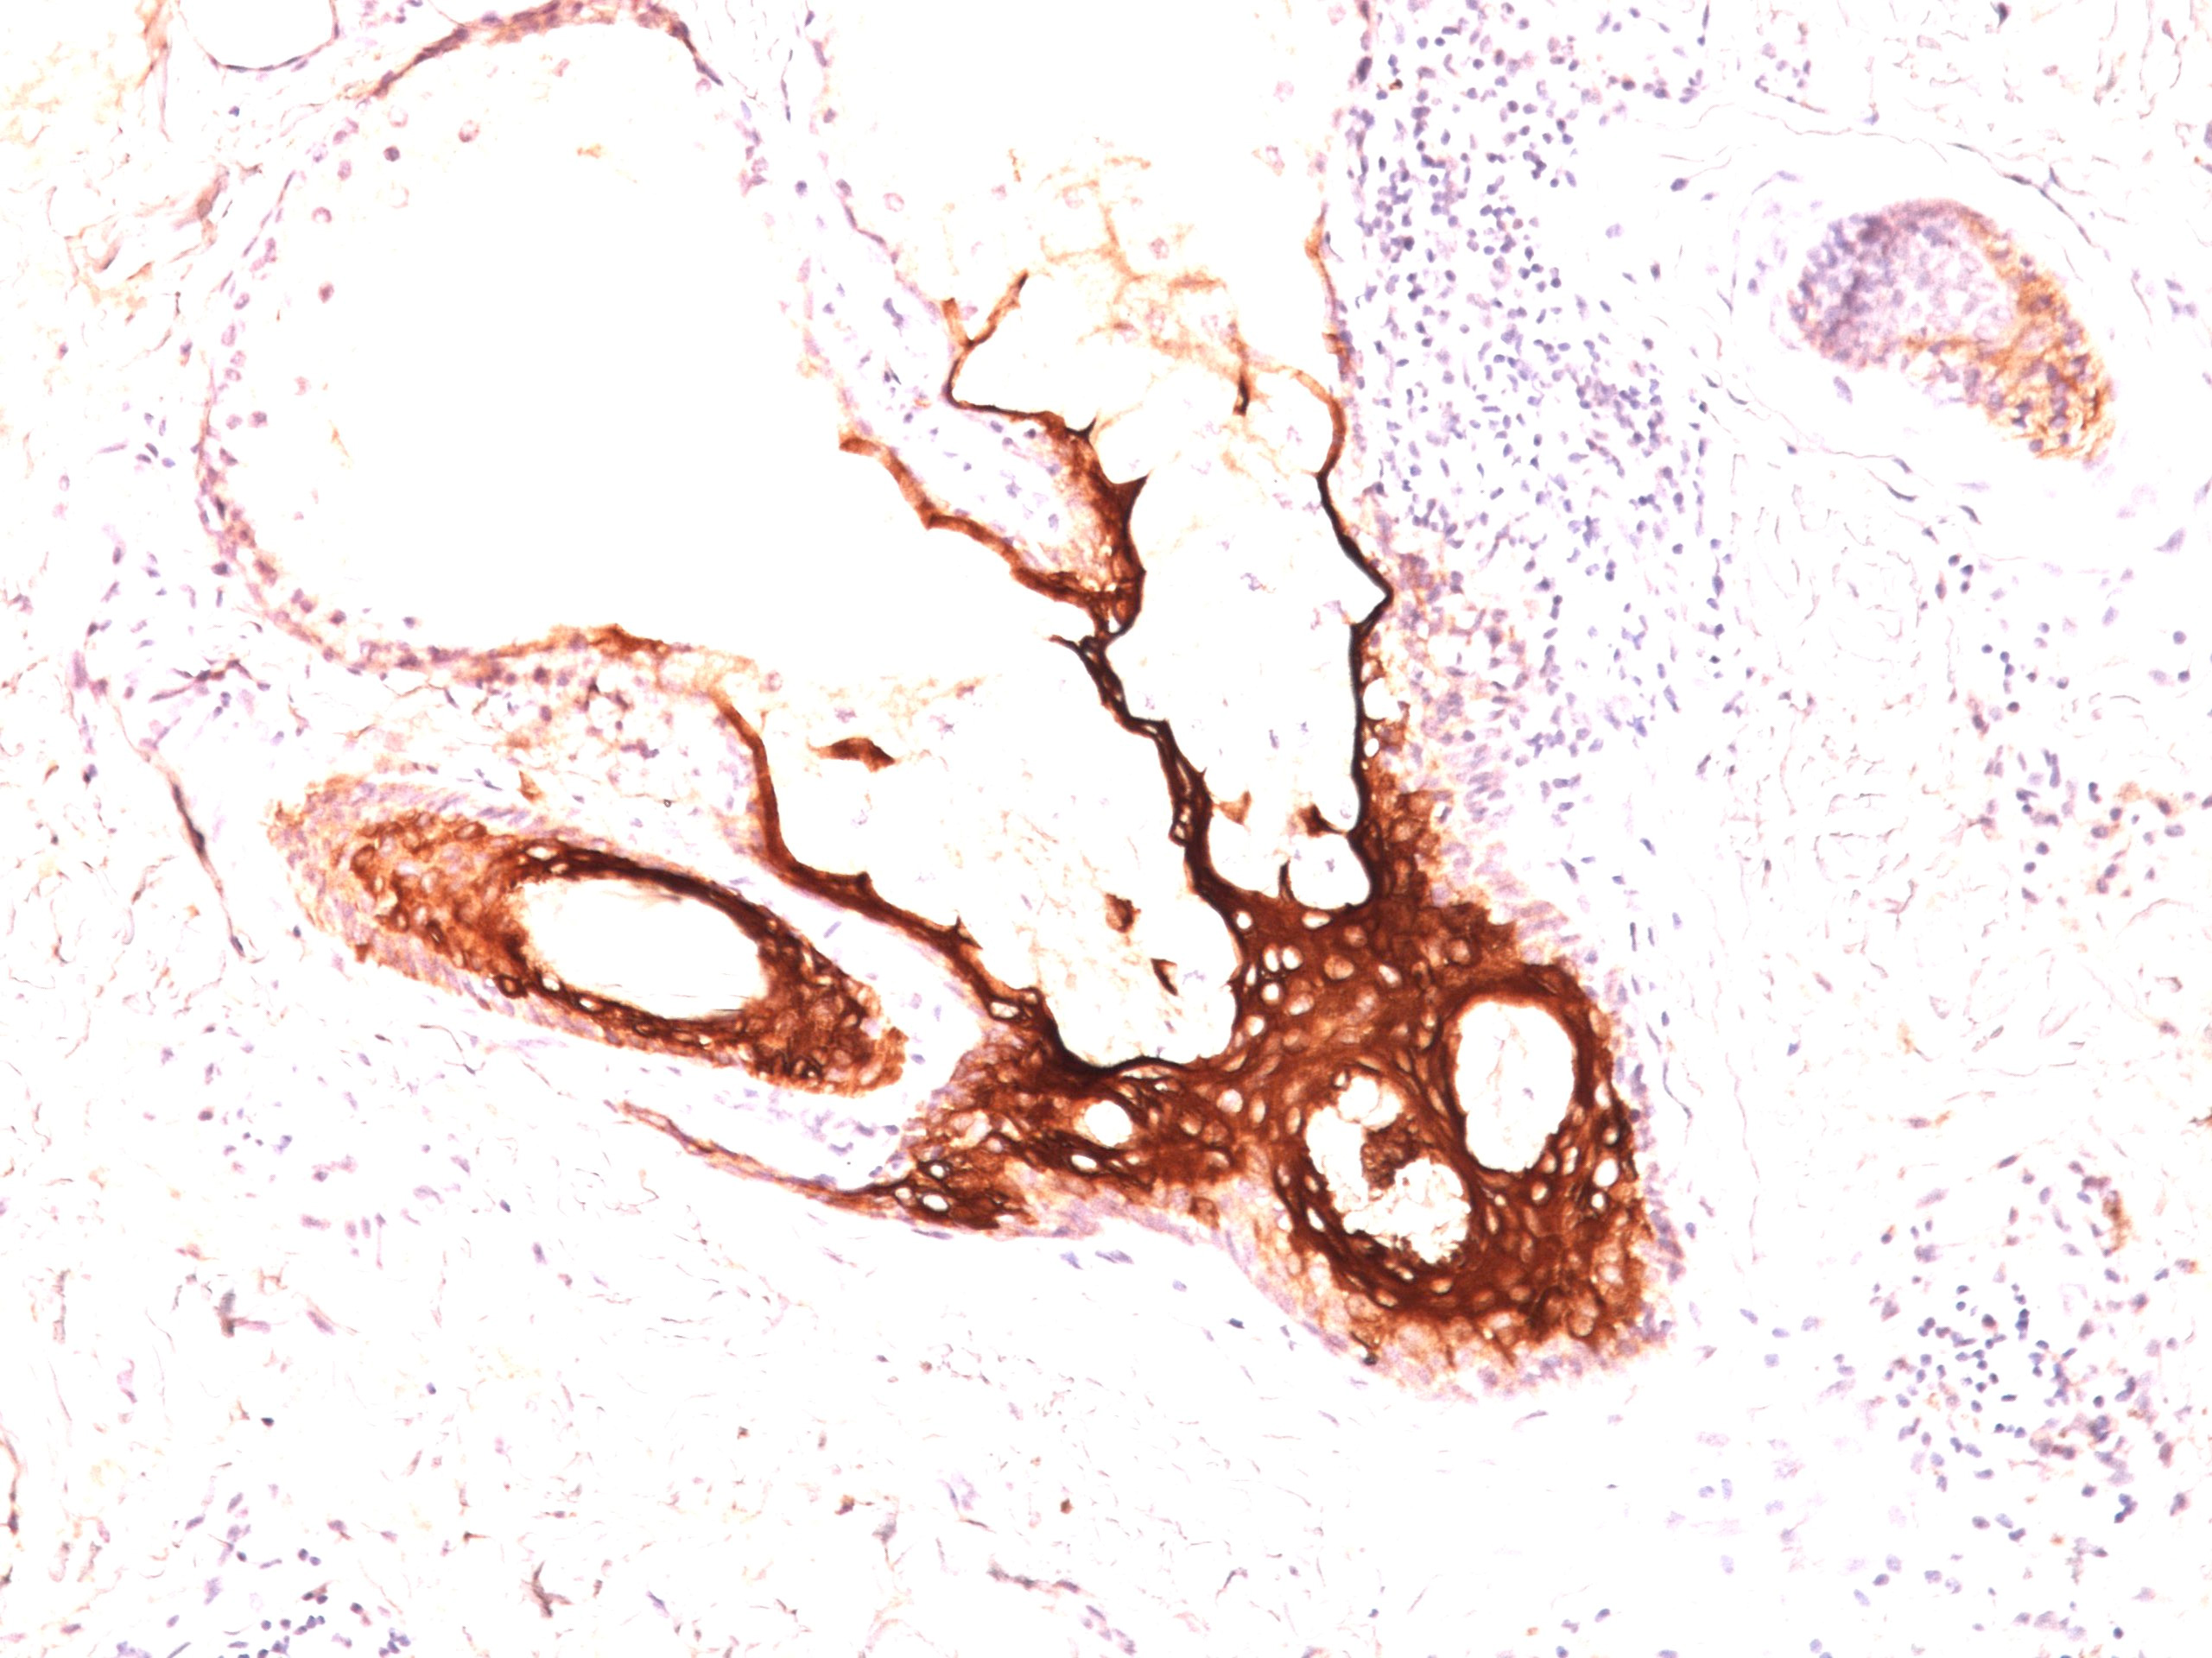

Formalin-paraffin skin stained with CK17 Ab (E3).